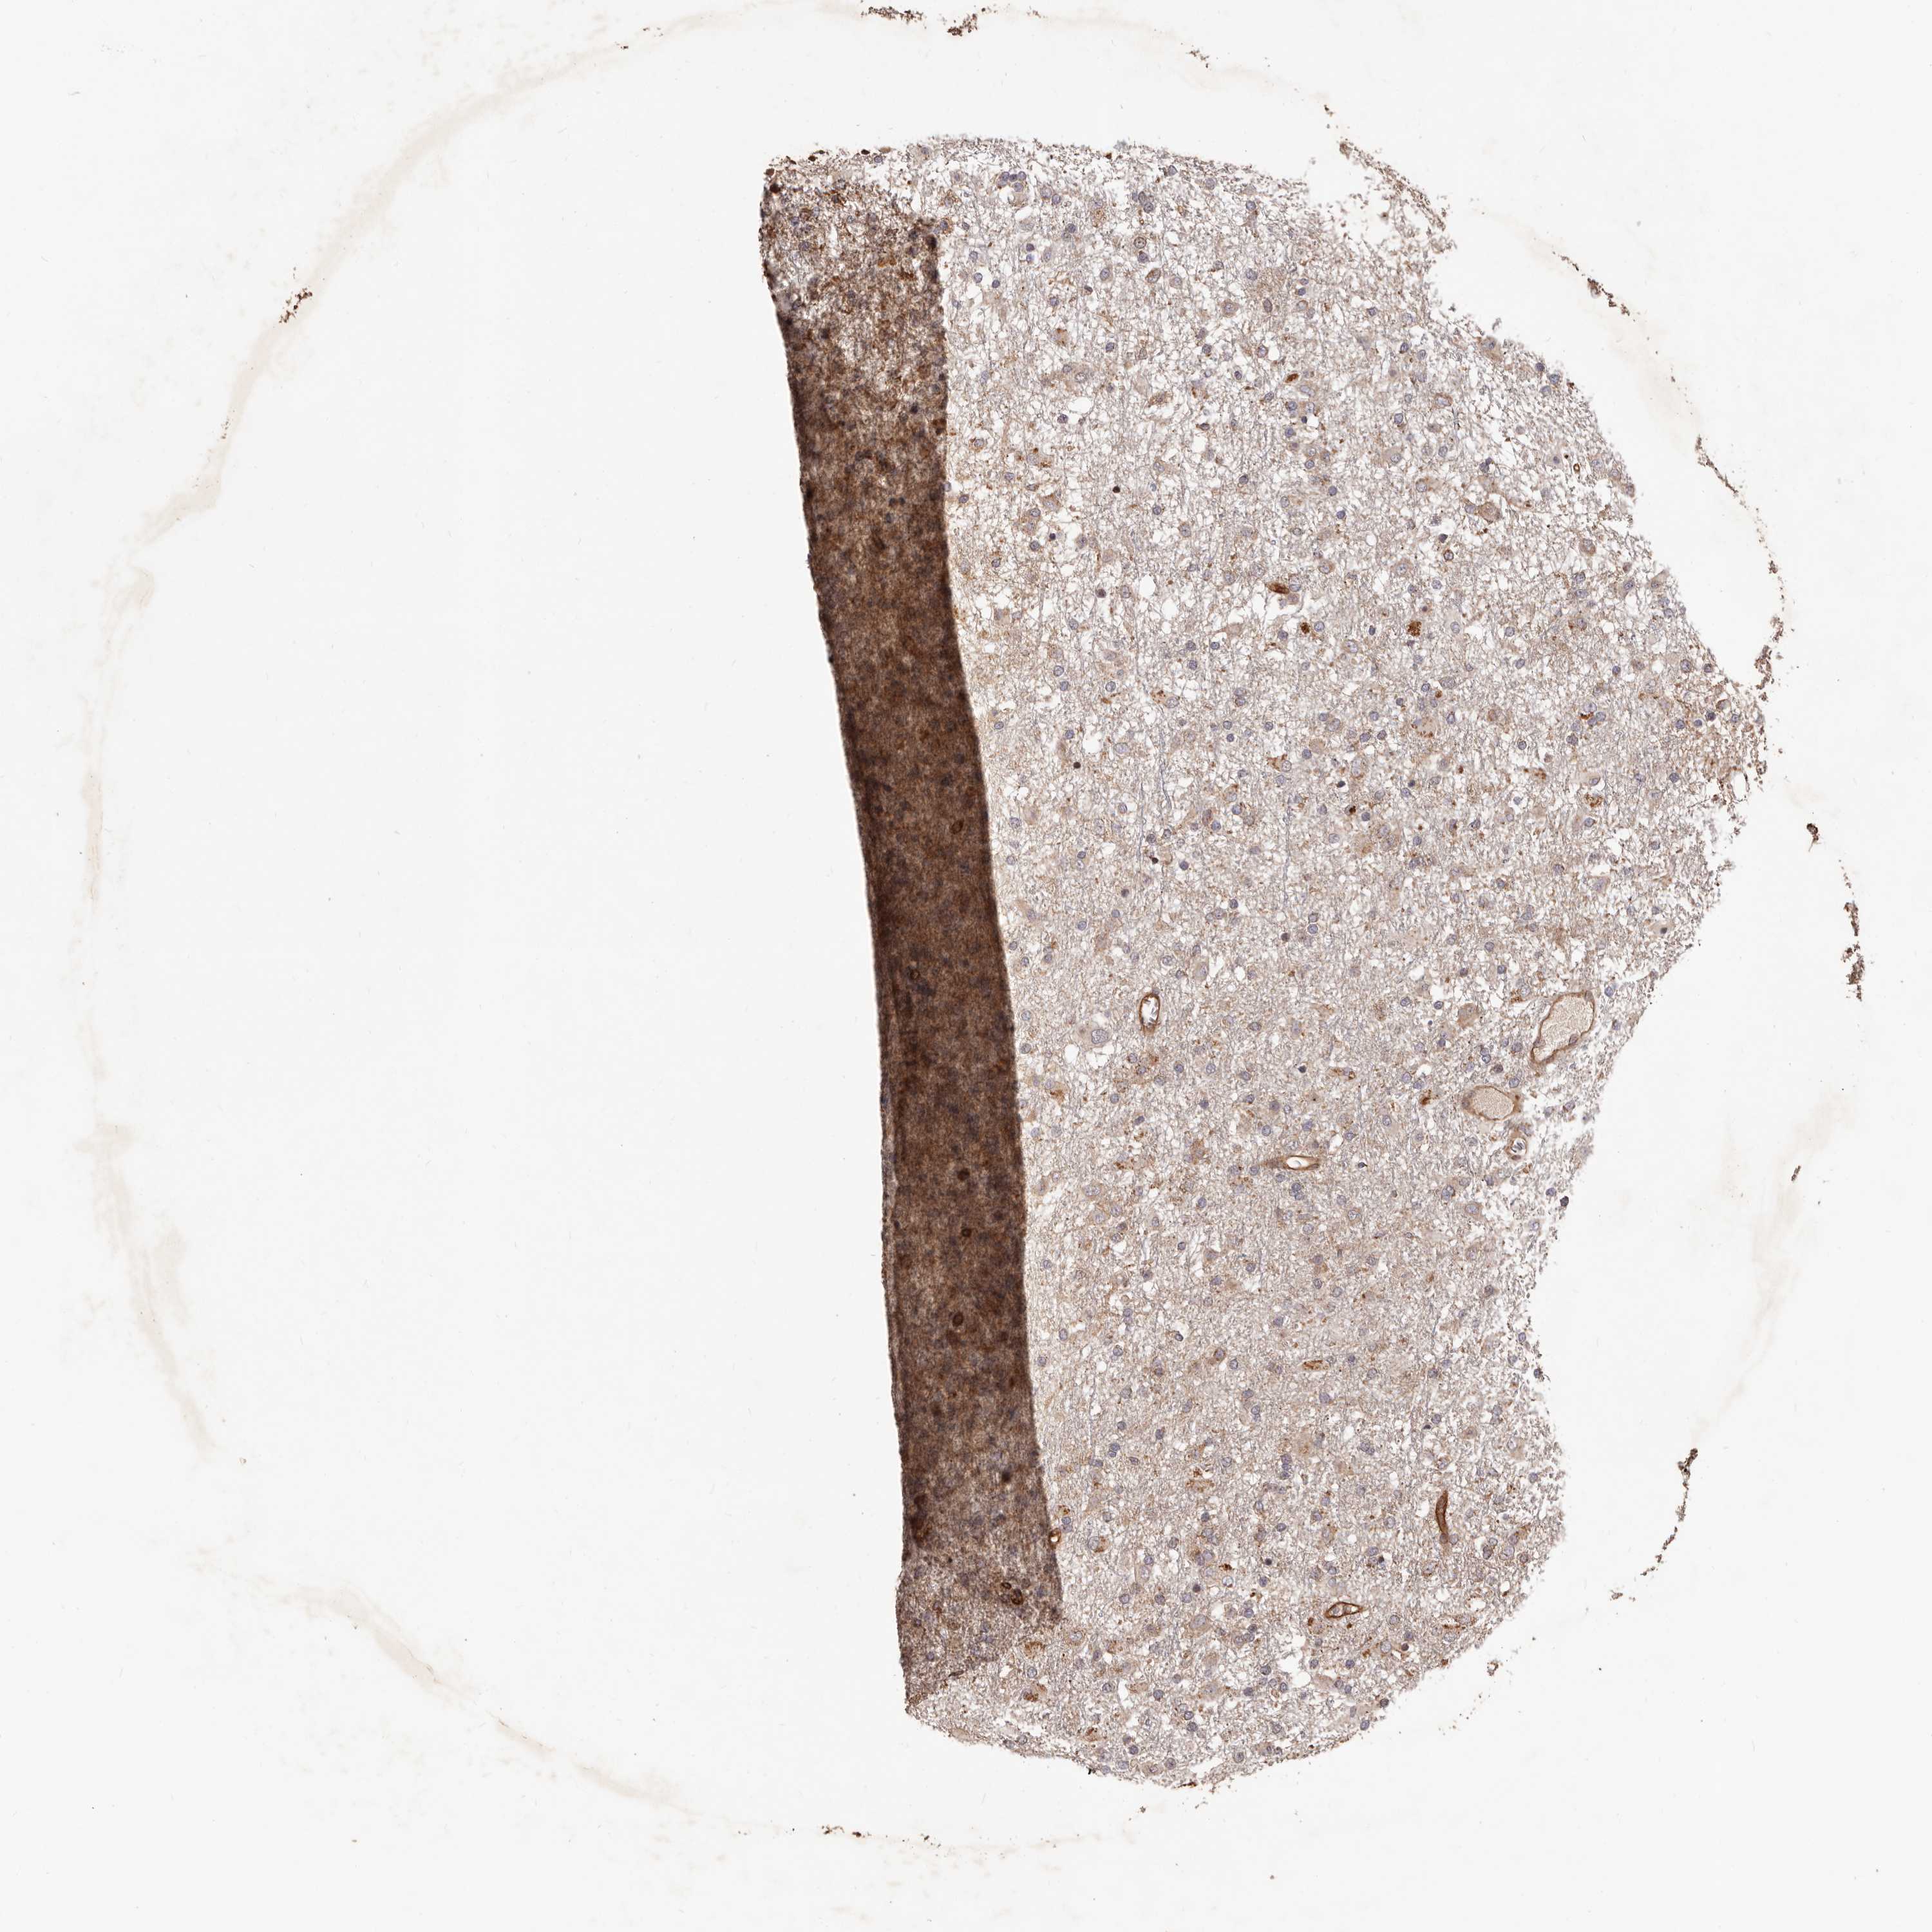

GLIOMA - Protein expressioni

A mouse-over function shows sample information and annotation data. Click on an image to view it in a full screen mode. Samples can be filtered based on level of antibody staining by selecting one or several of the following categories: high, medium, low and not detected. The assay and annotation is described here.

Note that samples used for immunohistochemistry by the Human Protein Atlas do not correspond to samples in the TCGA dataset.

Antibody stainingi

Antibody staining in the annotated cell types in the current human tissue is reported as not detected, low, medium, or high, based on conventional immunohistochemistry profiling in selected tissues. This score is based on the combination of the staining intensity and fraction of stained cells.

Each image is clickable and will lead to virtual microscopy that enables deeper exploration of all samples and also displays staining intensity scores, fraction scores and subcellular localization as well as patient and tissue information for each sample.

Antibody HPA003166

Antibody HPA064702

Staining

High

Medium

Low

Not detected

Intensity

Strong

Moderate

Weak

Negative

Quantity

>75%

75%-25%

<25%

None

Location

Nuclear

Cytoplasmic/membranous

Cytoplasmic/membranous,nuclear

Glioma, malignant, High grade

Glioma, malignant, Low grade